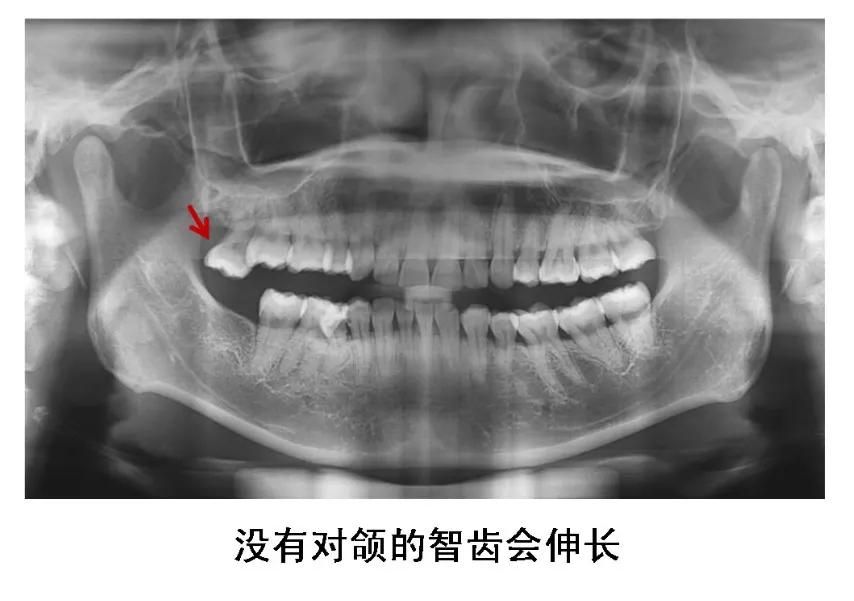

5、没有对颌牙的智齿

这种智齿不能与对颌牙齿建立正常咬合关系,长时间可导致颞下颌关节弹响、张口疼痛、夜磨牙等。没有对颌牙的智齿还会伸长,智齿和邻牙间容易食物嵌塞,并导致邻接面龋。

图片来源:作者提供